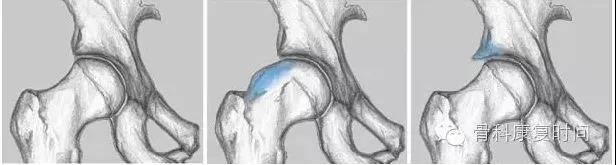

2、钳夹撞击型

- 通常存在于喜好活动的中年女性。

股骨头颈连接处和髋臼缘的异常接触,反复的撞击接触导致髋臼唇的变性,进一步引起髋臼内部囊性变以及髋臼唇周的骨化和髋臼加深。该慢性损伤常位于髋臼软骨周围的狭窄长条状区域。髋臼唇周围的变性通常以骨化形式表现。